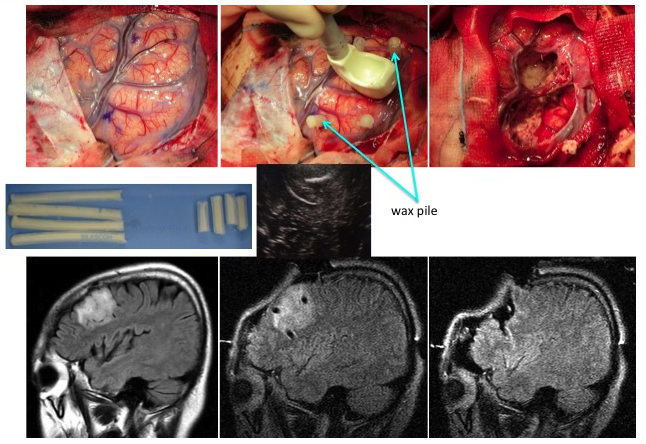

上段;術中所見

(左;摘出前、中;マーカー(シリコン製チューブ)挿入、右;摘出後)

下段;術中所見に準じた頭部MRI所見)